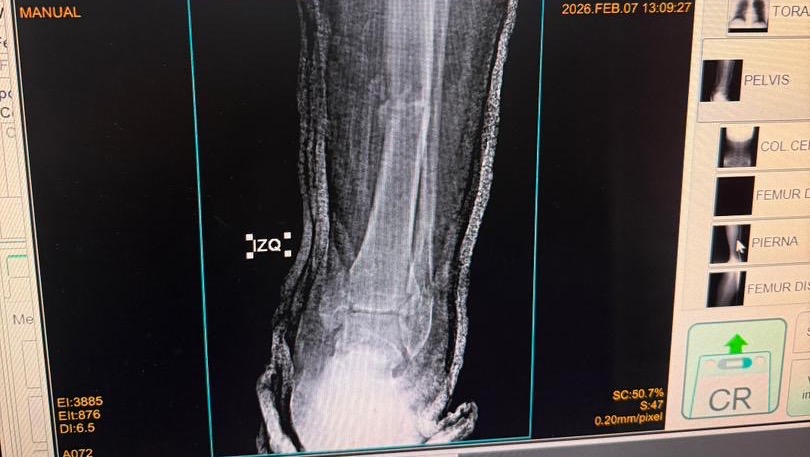

A sus 27 años, Jean Manuel Colella estaba cumpliendo una de sus metas más grandes: realizar sus prácticas universitarias en Barquisimeto, Venezuela. Sin embargo, la madrugada del 07 de febrero, su vida cambió en un segundo. Fue víctima de un terrible accidente automovilístico donde, lamentablemente, los responsables se dieron a la fuga, dejándolo atrás con heridas graves. Hoy, Jean Manuel enfrenta el reto más difícil de su vida. El accidente le causó múltiples fracturas en ambas piernas, siendo su pie derecho el más afectado. Para que él pueda volver a caminar, trabajar y terminar su carrera, necesita una cirugía de reconstrucción urgente. Cada granito de arena cuenta. Tu donación, por pequeña que parezca, es un paso más cerca de devolverle la movilidad a un joven que tiene todo un futuro por delante. ¡Ayúdanos a que Jean Manuel vuelva a ponerse de pie!

At the age of 27, Jean Manuel Colella was achieving one of his biggest goals: completing his university internship in Barquisimeto, Venezuela. However, in the early hours of February 7th, his life changed in an instant. He was the victim of a horrific car accident where, heartlessly, those responsible fled the scene, leaving him behind with severe injuries. Today, Jean Manuel faces the toughest challenge of his life. The accident caused multiple fractures in both legs, with his right foot being the most severely affected. In order for him to walk again, work, and finish his degree, he needs urgent reconstructive surgery. Every little bit helps. Your donation, no matter how small it may seem, is one step closer to restoring mobility to a young man with his whole future ahead of him. Help us get Jean Manuel back on his feet!